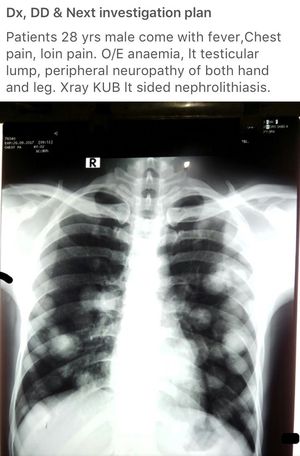

I think it maybe testicular cancer with metastas to lungs

Canon ball opacities..secondry mets lung

Sec Mets lung it may be testicular teratoma or something

Canon ball metastasis